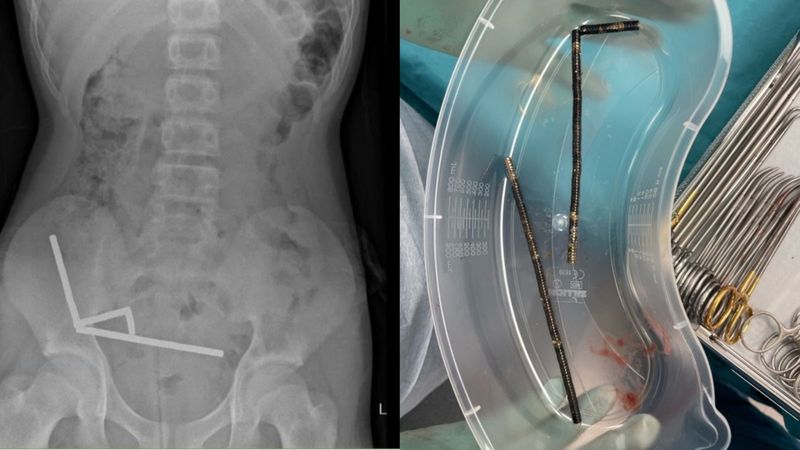

Dokter di Selandia Baru terpaksa mengeluarkan sebagian usus seorang remaja laki-laki berusia 13 tahun. Ini disebabkan adanya 100 magnet yang bersarang di usus. Foto: The New Zealand Medical Journal |

Setelah empat hari sakit perut, anak laki-laki berusia 13 tahun itu dirawat di Tauranga Hospital Selandia Baru, tempat para dokter menemukan magnet-magnet tersebut telah bergabung membentuk empat rantai di dalam ususnya.

Dalam jurnal medis yang diterbitkan di New Zealand Medical Journal, para ahli bedah mengekstraksi magnet-magnet tersebut dan mengangkat bagian-bagian usus anak laki-laki yang rusak.

Anak laki-laki itu, yang tidak disebutkan namanya dalam telah menelan "sekitar 80-100 magnet neodymium berdaya tinggi berukuran 5x2mm" seminggu sebelum dirawat di rumah sakit, kata para dokter. Ia dipulangkan setelah menghabiskan delapan hari di rumah sakit.